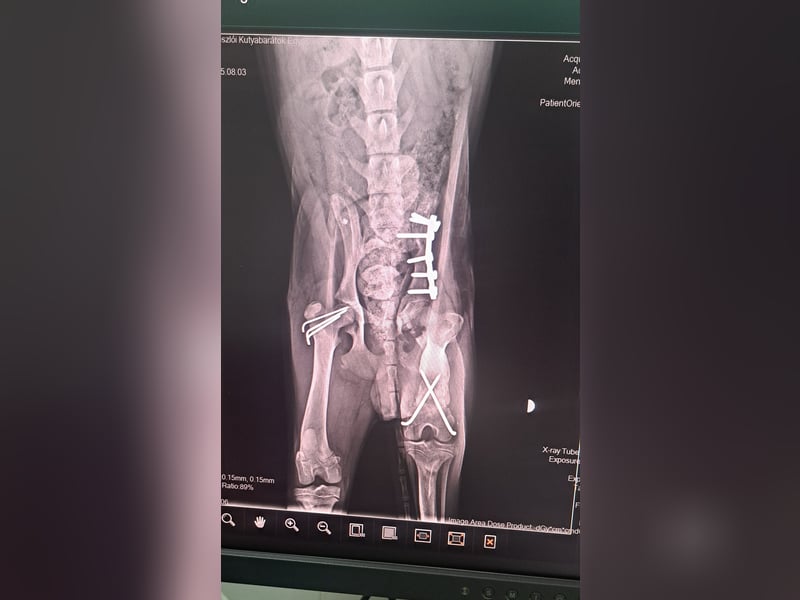

Der kleine Mango wurde von einem Auto angefahren und musste operiert werden.

Er hatte 3 Knochenbrüche, die mittlerweile gut verheilt sind.